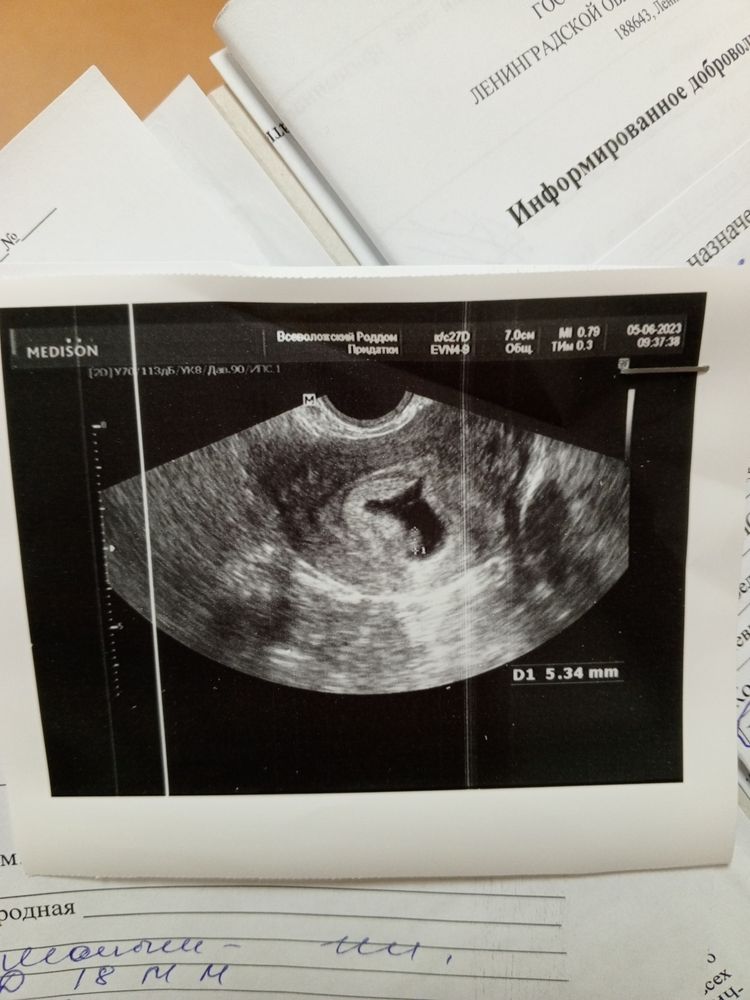

Результаты: УЗИ, КТГ, доплера, скринингаДевочки вообщем привет , про эту беременность я не писала здесь , но уже нет сил. В 5 недель и 1 день я попала с кровотечением в больницу , но ни отслоек ни гематом. Выписали всё ок. 24 мая было 6 недель и 5 дней. Съездила в роддом где отец мужа работает на узи сердцебиение послушать все супер. Прилагаю фото (синее сделано 24 мая, эмбрион 8.3)

И чёрное белое узи это сегодня (эмбрион 5.3) что соответствует сроку 6.1 что-то такое.....

Аня Михайлова, 24 мая был ктр 8.3 и сердцебиение 93. А сейчас ктр 5.3 и они не понимают говорят